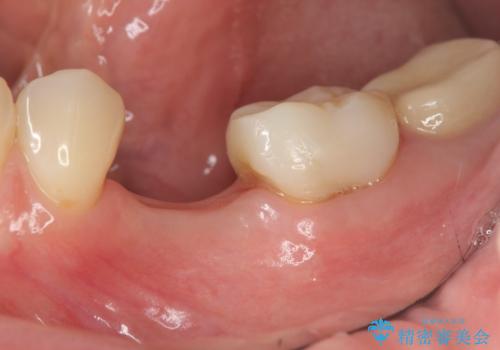

- 44万円(仮歯・ジルコニアクラウン・インプラント・アバットメント)費用は治療当時の料金となります

残念ながらぐらつきが大きくなり、残すことが難しくなり抜去したのちインプラントを用いて咬合機能の回復をしっかりと行いました。